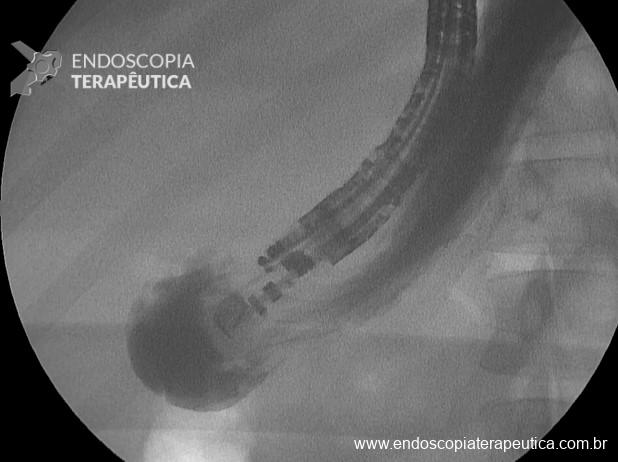

- Administrar contraste iodado pela agulha (optar por seringas pequenas e contraste iodado (diluído em 50% com soro fisiológico), confirmando e dilatando o estômago excluso por ecoendoscopia e fluoroscopia (Figura 4);

- Conectar a agulha com uma bomba de água adaptada com luer lock e preencher com soro fisiológico até distender o estômago de forma segura (distender com ao menos o diâmetro de uma coluna vertebral (estimado em 2,5 cm);

- Repuncionar com FNA 19G, em corpo proximal e distender o estômago excluso novamente com soro fisiológico em bomba até ter uma janela de punção com lúmen de ao menos 3 cm e visualizar o contraste em fundo (Figura 5);